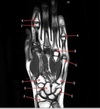

6

Q

What is letter D?

A

SUPRASPINATUS MUSCLE

How well did you know this?

1

Not at all

2

3

4

5

Perfectly

7

What is letter A?

SUBSCAPULARIS MUSCLE